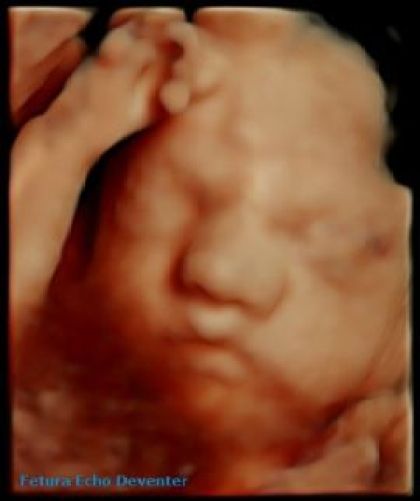

Een 3D-pretecho is een mooie en speciale manier om je baby al te zien voordat hij of zij geboren wordt. Tijdens de echo kun je je baby in 3D zien, wat het mogelijk maakt om bijvoorbeeld het gezichtje en de bewegingen duidelijk te bekijken.

De beste termijn om een 3D echo te maken is tussen de 24 en 27 weken. Voor het maken van mooie beelden zijn we erg afhankelijk van de ligging van de baby, de hoeveelheid vruchtwater en of er armen of een navelstring voor ligt.